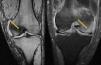

Clinical CaseA 41 year old male with no medical history of interest, presented at the surgery with right knee pain and minimum trauma. Diffuse bone marrow oedema involving the external condyle was reported. Four months later he presented with bone marrow oedema in the ipsilateral internal condyle (Fig. 1). In other magnetic resonance images we found new bone marrow oedema extension, in the internal femoral condyle of the contraleteral knee and later in the external condyle and pain in the right knee, the NMI of which also showed bone marrow oedema (Figs. 2 and 3). Treatment with NSAIDS was administered and partial load-bearing but this was ineffective.

In the differential diagnosis its distinction is interesting, compared with the algodystrophy of Südeck, reflex sympathetic dystrophy or complex regional pain syndrome. This condition is painful after a traumatic event, sometimes with low intensity, and presents with allodynia (or intense pain on response to non painful stimuli), hyperalgesia, and vasomotor disorders with vegetative symptoms. In transient migratory osteoporosis these vegetative symptoms do not arise. Furthermore, the marrow bone oedema presents as an imaging pattern in the NMI characterised by low-intensity signals in T1 and high-intensity signals in STIR T2 in bone marrow. When this oedema appears in several joints without osteonecrosis images, and not in any isolated form, we would diagnose a transient migratory osteoporosis.